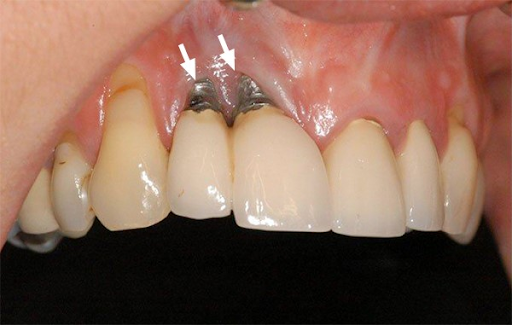

Răng bị viêm nha chu

Đây là một tình trạng viêm nhiễm mạn tính và có thể gây tổn thương cho xương hàm và răng. Nếu không được điều trị kịp thời hoặc điều trị không đúng cách, bệnh có thể dẫn đến mất răng và gia tăng nguy cơ mắc các vấn đề nghiêm trọng khác về sức khỏe như đột quỵ, đau tim… Tuy nhiên, nếu được phát hiện sớm và duy trì vệ sinh răng miệng hợp lý, viêm nha chu có thể được điều trị hiệu quả.